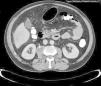

Se incluyeron 30 pacientes con AP, 25 piógenos y 5 tuberculosos, En 9 ocasiones fueron primarios y en 21 secundarios (a patología esquelética en 8 a patología urológica en 8 y a gastrointestinal en 8). No se observaron diferencias clínicas entre ambos grupos. Los pacientes con AP piógenos tendieron a tener mayores cifras de leucocitos (13.871 vs. 8.560/mm3, p=0,018) y de velocidad de sedimentación globular (VSG) (108 vs. 17mm/h, p<0,0001) y menores de hemoglobina (11 vs. 14g/dL, p=0,008) Se diagnosticaron por tomografía computarizada (TC) en 29 pacientes y por resonancia magnética en 1, ambas con una sensibilidad diagnóstica del 100%, frente al 50% de la ecografía. La lateralidad izquierda fue menos frecuente en los AP piógenos (44 vs. 100%, p=0,031). Los hemocultivos y el cultivo de pus del absceso fueron positivos en el 22% y 82% de las ocasiones en las que se realizó. Los gérmenes aislados con más frecuencia fueron bacilos gramnegativos, Streptococcus spp. y S. aureus. El 50% de los casos fueron drenados percutáneamente, el 13% quirúrgicamente y el 3% por ambas técnicas. Fallecieron 2 pacientes, ambos con absceso piógeno.

Los abscesos piógenos secundarios constituyen el grupo de AP más frecuente. La TC es el procedimiento diagnóstico de elección. La presencia de leucocitosis, anemia, VSG elevada y la lateralidad derecha sugieren etiología piógena. El drenaje percutáneo está sustituyendo al quirúrgico y permite obtener muestras diagnósticas.

Thirty PA were included, 83% pyogenic and 17% tuberculous, average age 53 years. On 9 occasions, 30% were primary and on 21 occasions, 70% secondary (to skeletal pathology in 8, to urological in 8 and to gastrointestinal in 8). No clinical differences were observed between both groups. Pyogenic and tuberculous etiologies were differentiated analytically through leukocyte values (13,871 vs. 8,560/mm3, p=0.018), hemoglobin (11 vs. 14g/dL, p=0.008) and erythrocyte sedimentation rate (ESR) (108 vs. 17mm/h, p<0.0001). Abscesses were diagnosed by computed tomography (CT) in 29 patients (97%) and by magnetic resonance in 1 (3%), both with a diagnostic sensitivity of 100%, as opposed to 50% for ultrasound scanning. Left laterality was less frequent in pyogenic abscesses (44% vs. 100%, p=0.031). The blood cultures were positive in 22% and abscess pus culture in 82%. Gram negative bacilli, Streptococcus spp. and S. aureus were the most frequent isolations. A total of 67% were drained: transcutaneously 50%, surgically 13% and both techniques 3%. Two patients died (7%), both with pyogenic abscess.

Secondary pyogenic abscesses constitute the most frequent PA group. CT is the diagnostic procedure of choice. Leukocytosis, anemia, raised ESR and right laterality suggest pyogenic etiology. Transcutaneous drainage is substituting surgical drainage and also makes it possible to obtain diagnostic samples.